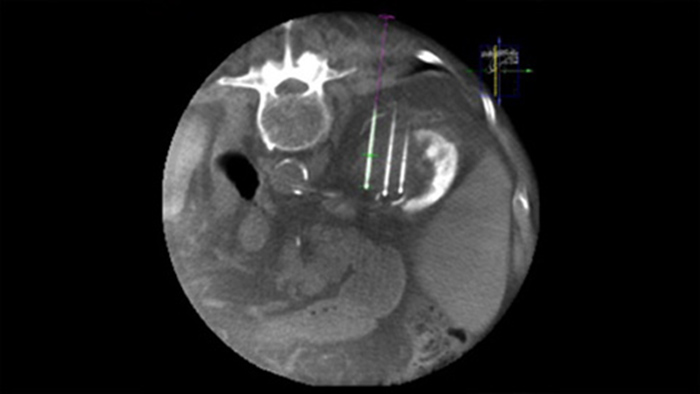

SmartCT Soft Tissue offre une technique d’acquisition CBCT (Cone Beam CT) complétée par un guidage pas à pas des outils de visualisation 3D et de mesure avancés, tous accessibles sur le module à écran tactile depuis la table.

Le double affichage permet de superposer une image 3D avant la procédure (TDM/IRM/TEP-TDM) sur une image CBCT 3D double affichage au cours de la procédure pour mieux visualiser les lésions et accéder aux données critiques pour la planification des aiguilles.

Une navigation précise à faible dose vers la lésion concernée sans repositionnement de l’aiguille augmente les chances de réussite et réduit le risque de complications de vos biopsies ou de vos ablations. La confirmation du point final du traitement d’ablation s’effectue avec l’imagerie 3D lorsque le patient est encore sur la table.